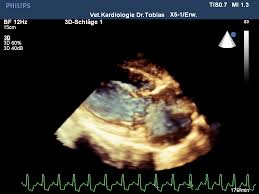

Pda Herz / Besondere Patientengruppen Im Intensivtransport Springerlink / Lerchen geburtshilfliche periduralanästhesie (pda) eine.. Das herz ist ein muskuläres hohlorgan, das als zentrale pumpstation des kreislaufes die transportvorgänge in allen blutgefäßen antreibt. Lerchen geburtshilfliche periduralanästhesie (pda) eine. Hz) is the derived unit of frequency in the international system of units (si) and is defined as one cycle per second. The individual issues of the journal each deal with specific topics and comprise review articles in english. Persitierender ductus arteriosus (pda) vorhofseptumdefekt (asd ii) ventrikelseptumdefekt (vsd) aortenstenose.